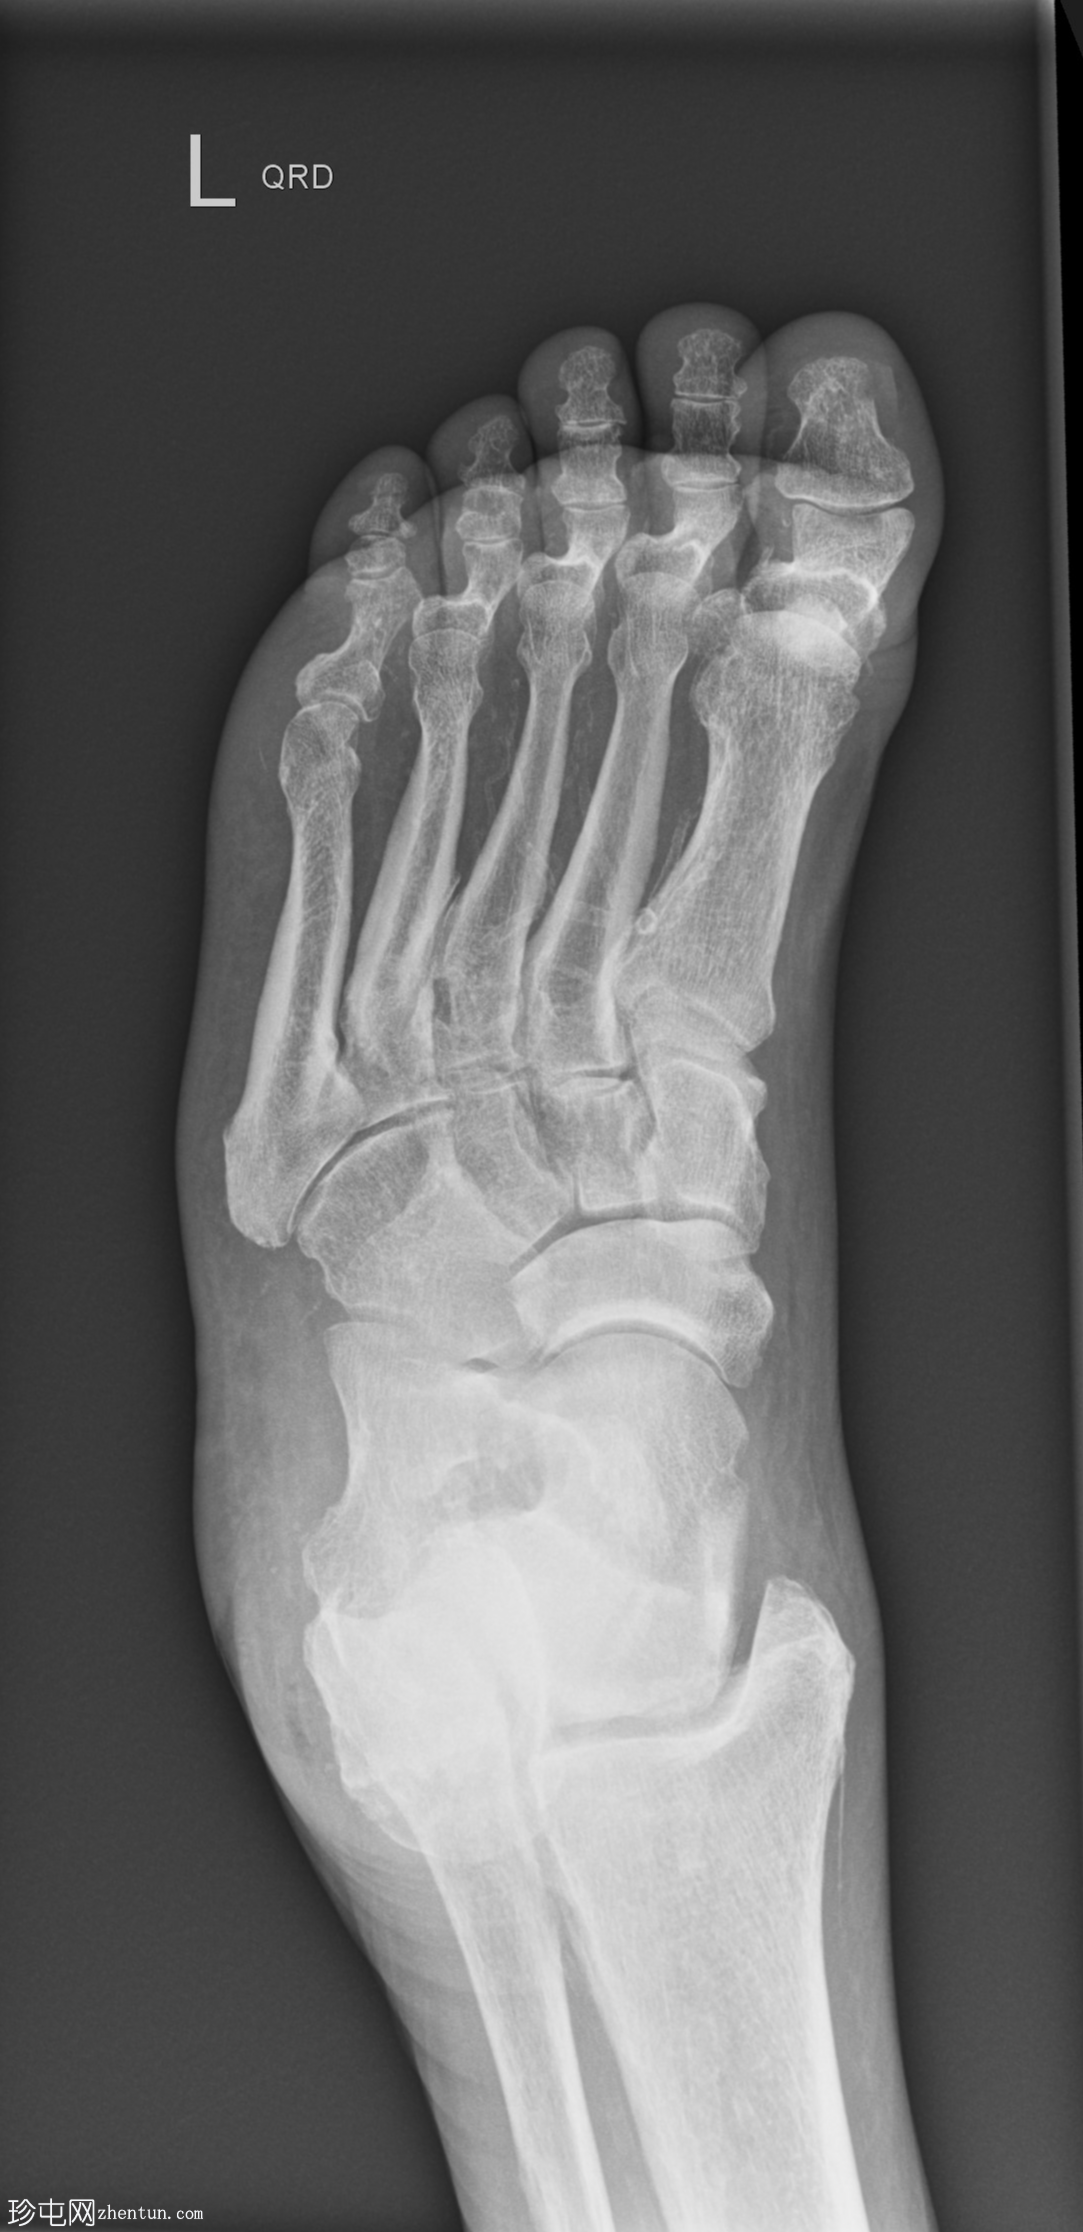

正位片

跖趾关节爪状趾畸形

动脉钙化

爪状趾畸形是指小趾跖趾关节过度伸展,导致近端指间关节(PIP)和远端指间关节(DIP)屈曲。